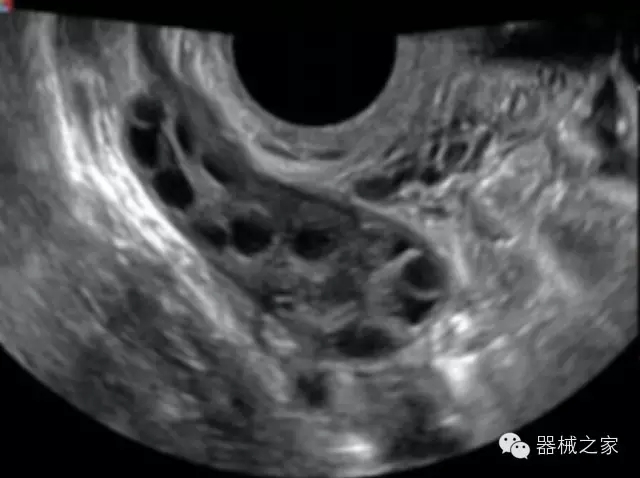

經(jīng)典產(chǎn)品:S8EXP

臨床圖片賞析

產(chǎn)品特點(diǎn)

優(yōu)異的成像技術(shù)

·亞陣元技術(shù):獨(dú)有的亞陣元技術(shù),對獨(dú)立晶片做二次切割,減少旁瓣偽像,增加臨床診斷的準(zhǔn)確性;

·μ-Scan微米成像技術(shù):開立獨(dú)有的μ-Scan技術(shù),還原出真實(shí)細(xì)膩、層次對比優(yōu)異的二維圖像;

·倒相諧波成像技術(shù):倒相諧波技術(shù)在去除基波信號的基礎(chǔ)上獲取兩倍二次諧波信號,提高組織圖像的對比分辨力;

·智能微血流成像技術(shù):智能微血流捕捉技術(shù)可以提取出隱藏在背景噪聲中的弱血流信號,大大提高低速血流的敏感性;

全面的臨床解決方案

超聲科常規(guī)領(lǐng)域應(yīng)用

·移植S40高端臺式彩超高端平臺技術(shù),滿足超聲科腹部、淺表、婦產(chǎn)科、心血管、肌骨等應(yīng)用,提供超聲科完美解決方案;

·實(shí)時的彈性成像技術(shù):提高了小器管(乳腺,甲狀腺、淺表軟組織腫瘤等)疾病鑒別診斷;

·IMT血管內(nèi)中膜自動測量:為血管性疾病評估提供了有效的評估手段;

·心功能綜合指數(shù)(TEI指數(shù)):用于左、右心室整體心臟收縮舒張功能評估的測量方法;

·全方位可調(diào)M型:有利于更好的觀察心腔大小及室壁階段性運(yùn)動的異常情況;

·組織多普勒成像(TDI):TDI可定量評價心肌運(yùn)動,判斷是否有局部病變,還可評價早期的舒張功能;

·高效3D/4D成像技術(shù):高速的4D幀頻,豐富的3D成像模式,智能斷層切片功能;